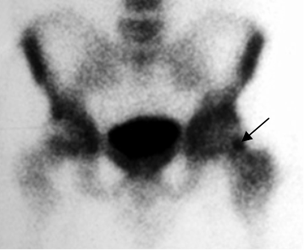

Fig 61. Osteoma osteoide.

Gamagrafía. Aumento de la captación en el cuello femoral izquierdo, por osteoma osteoide.